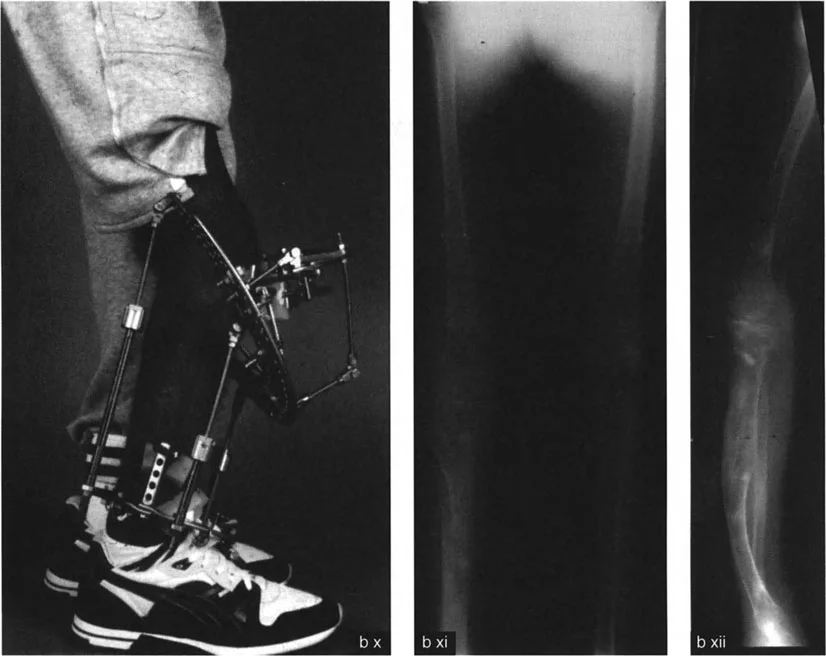

بالنسبة للمرضى الذين يعانون من تشوهات معقدة، خاصة تلك التي تؤثر على عظم الساق (الظنبوب) وتظهر على شكل انحناءات متعددة المستويات، فإن فهم هذه التعقيدات أمر بالغ الأهمية. هذه الحالات غالبًا ما تتطلب أكثر من مجرد تدخل جراحي بسيط؛ فهي تتطلب خبرة جراح ماهر يفهم لماذا تفشل عمليات قطع العظم أحادية المستوى في مواجهة التقوسات الشاملة أو الانحرافات الزاوية المعقدة متعددة المستويات.

من خلال هذا الدليل الشامل، سنسلط الضوء على الميكانيكا الحيوية الكامنة وراء حلول قطع العظم أحادية مقابل متعددة المستويات، ونكشف عن المخاطر الخفية في تصحيح التشوهات، مثل الكشف غير المقصود عن مفصل ذي اتجاه خاطئ. في صنعاء، يقود الأستاذ الدكتور محمد هطيف، استشاري جراحة العظام والعمود الفقري، هذا المجال بفضل خبرته الواسعة وتطبيقه لأحدث التقنيات العالمية في تشخيص وعلاج انحرافات الساقين المعقدة، مما يجعله المرجع الأول للمرضى الباحثين عن حلول متقدمة ودقيقة.